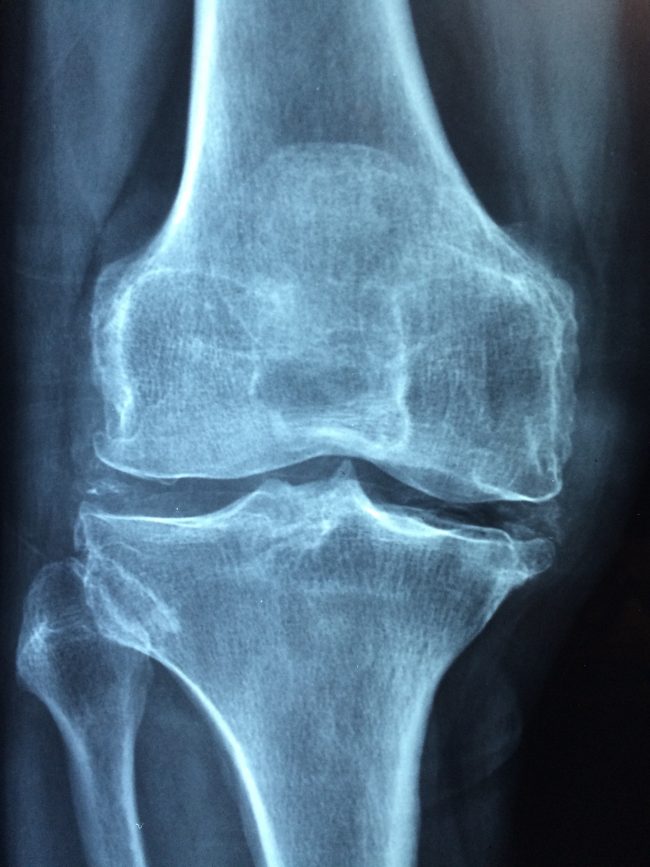

Cuando tu abuela dice que son CRECEDERAS y tu médico lo llama Enfermedad de Osgood-Schlatter

La enfermedad de Osgood-Schlatter u Osteocondrosis juvenil, coloquialmente «crecederas«, es un crecimiento doloroso de la protuberancia de la tibia, justo debajo de la rodilla (tuberosidad tibial), donde se inserta el tendón rotuliano. ¿A QUIÉN AFECTA? Consiste en una inflamación dolorosa en la región antero-inferior de la rodilla, que es más frecuente en adolescentes de 10 a 15 años de edad, sobre todo cuando se encuentran en un periodo de…